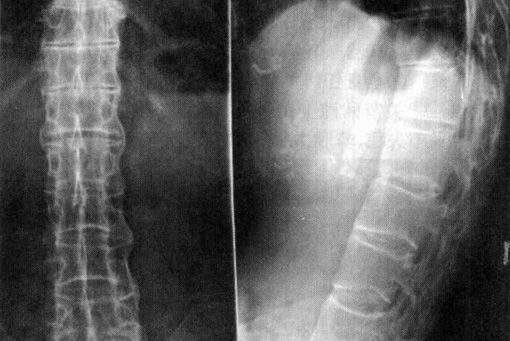

AS ①晚期 ②重度 病史:5年+

治疗后骶髂关节疼痛消失,腰椎前屈、背伸侧弯活动自如,膝关节无压痛感,复查血沉、C反应蛋白、等各项检查均已达到临床康复的标准。